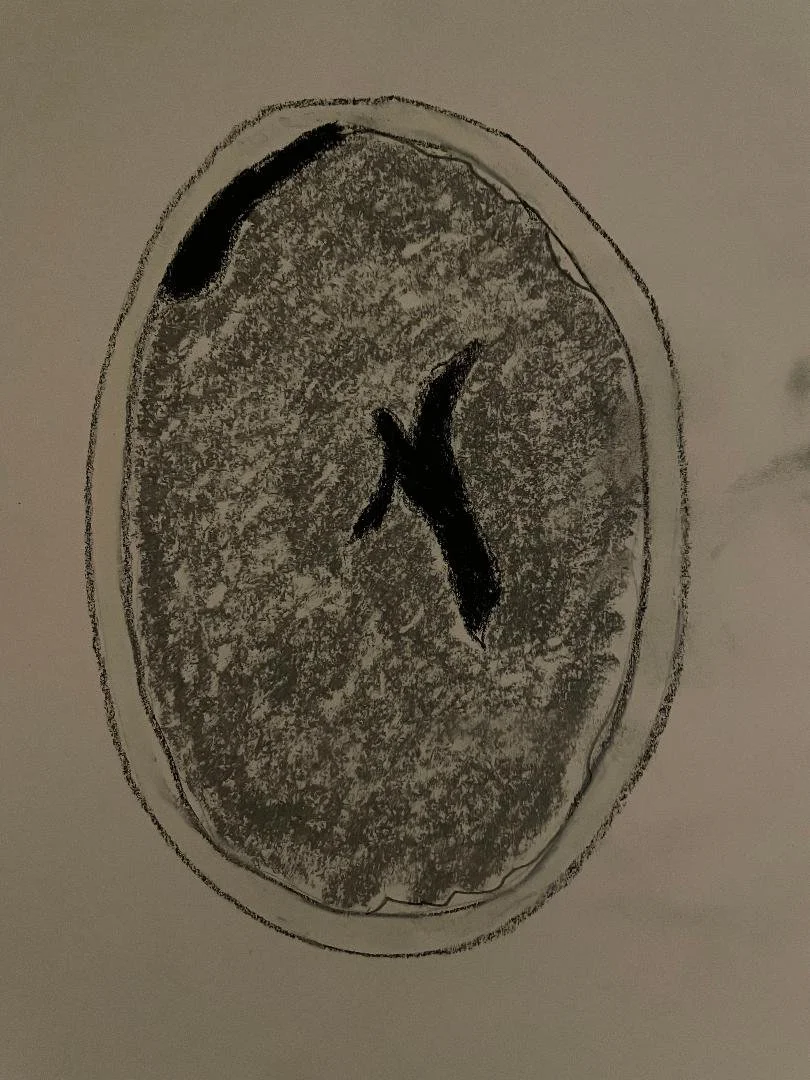

Tuberous sclerosis